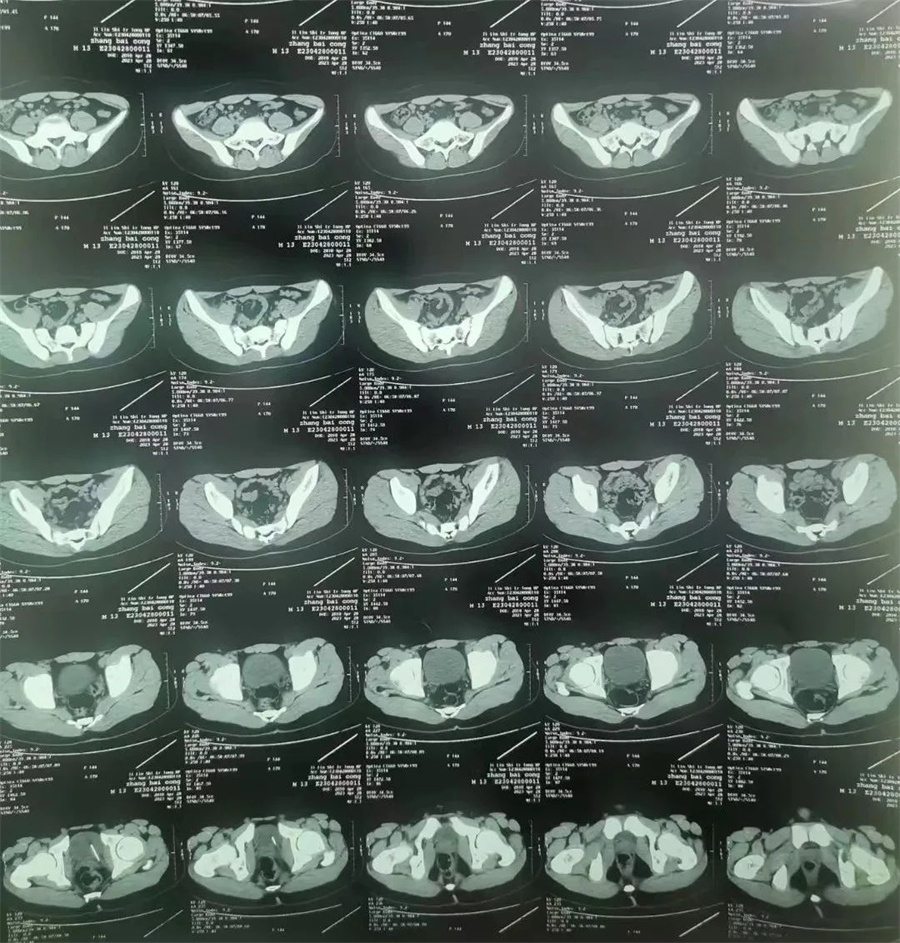

斌斌(化名),13岁,家住吉林市,因尿道疼痛、内裤有血,被家长带到当地医院就诊。医生经CT检查,发现斌斌膀胱侧壁扎着一根针,随时有穿破膀胱壁、损伤周围脏器可能。医生建议家长立即带斌斌到啪啪网 进行手术,将针取出。

。泌尿外科主任谢方达为其开辟绿色通道,以最快的速度进行救治。谢方达主任利用膀胱镜探查,很快确认了针在膀胱内的具体位置。

由于针已经在膀胱内存留一年多,表面布满铁锈和陈渣,加之男孩尿道细长弯曲。如果强行经尿道取针,发生副损伤或尿道内异物存留的风险极大。

如何简捷、确切、迅速地将针取出成了最大难题。最终,谢方达主任决定利用腹腔镜在患儿膀胱上打孔,进行微创取针。当长度约4厘米、表面锈迹斑斑的针呈现在众人面前时,家长紧张焦虑的心情终于缓解了。

术后,谢方达主任说,经过长时间的腐蚀,针变得非常脆,一夹就碎,不断掉渣,好在经过灌洗,残渣被冲洗干净了。